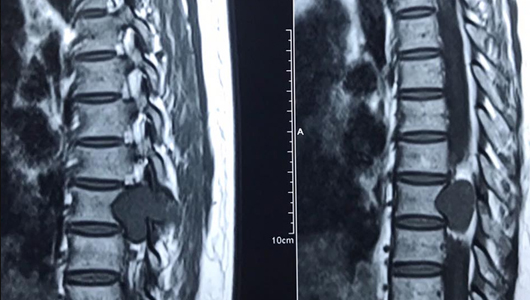

Lồi đĩa đệm L4 L5

L4 và L5 là vị trí xuất hiện tình trạng lồi đĩa đệm phổ biến hơn cả. Đây là các đốt sống thấp nhất trong toàn bộ cột sống thắt lưng. Chúng phải chịu những áp lực lớn nhất khi có bất kỳ một tác động nào đè lên cột sống. Do đó, sẽ có nhiều tổn thương xảy ra ở 2 đốt sống L4 và L5 này hơn, trong số đó chính là phồng lồi đĩa đệm. Tuy nhiên, tình trạng lồi đĩa đệm L4 và L5 vẫn có thể được coi là tình trạng phồng lồi nhẹ.

Nguyên nhân chính dẫn đến hiện tượng này là do ảnh hưởng từ sự lão hóa của xương khớp, hoặc ảnh hưởng từ chấn thương do va đập mạnh,... Người bị lồi hoặc thoát vị đĩa đệm cột sống thắt lưng thường cảm thấy đau, nhức mỏi ở vùng thắt lưng mỗi khi đứng hoặc ngồi quá lâu ở một tư thế. Các cơn đau này thường xuất hiện nhiều hơn vào ban đêm, sáng sớm hoặc mỗi khi thời tiết thay đổi. Tình trạng này sẽ khiến người bệnh di chuyển, đi lại khó khăn hơn về lâu dài.

Lồi đĩa đệm L5 S1

Nếu như L4 L5 là các đốt sống nằm thấp nhất ở cột sống, thì L5 và S1 là 2 đốt sống được coi là điểm tựa chính của cột sống, đóng vai trò quan trọng giúp chúng ta thực hiện được những động tác phức tạp ở cột sống như cúi, ưỡn hay nghiêng người,... Việc hoạt động thường xuyên, thay đổi tư thế ở phần lưng sẽ khiến đốt sống L5 và S1 chịu nhiều tổn thương hơn nên dễ dẫn đến tình trạng lồi đĩa đệm.

Lồi đĩa đệm L5 S1 sẽ khiến đĩa đệm ở hai vị trí này Lồi và lồi ra sau, tuy nhiên nhân nhầy vẫn chưa thoát ra hẳn khỏi bao xơ. Do vậy sẽ gây ra một biến chứng khác, đó là bị thoát vị đĩa đệm. Loại lồi đĩa đệm này cũng khiến cho người bệnh cảm thấy đau nhức ở vị trí L5 S1, đồng thời hạn chế về khả năng vận động.